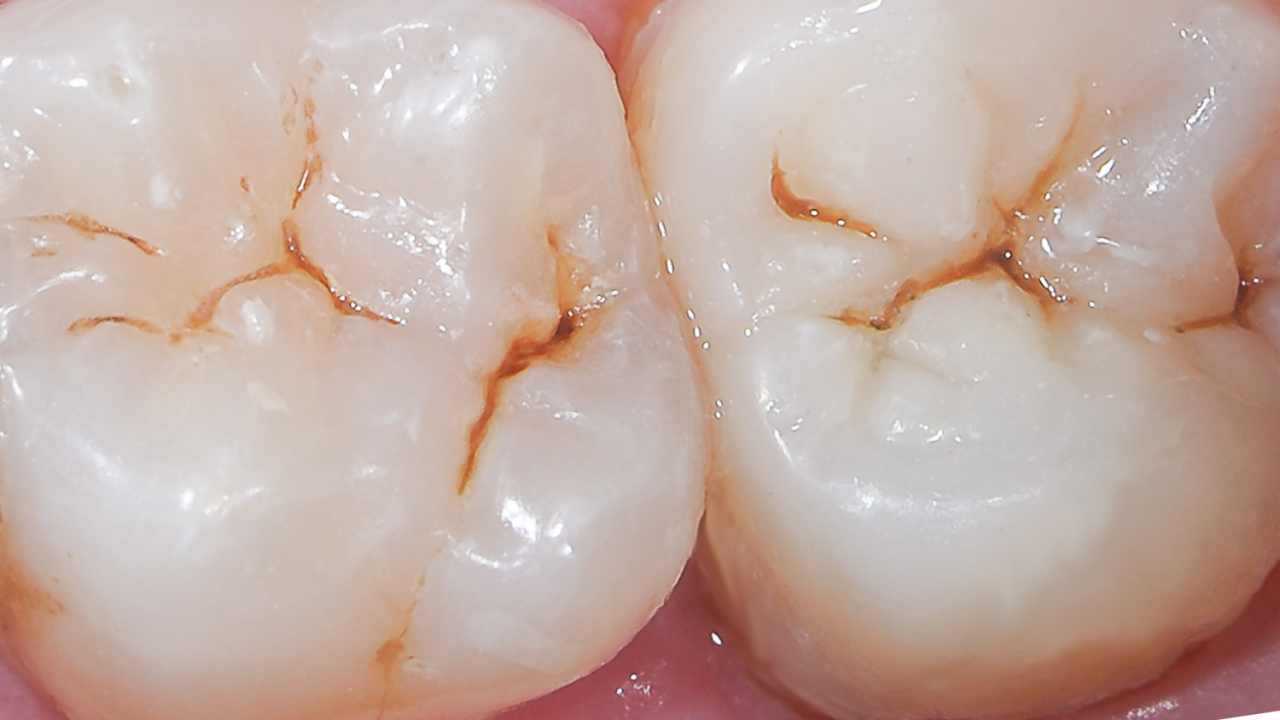

Marginal elevation

Case: In cases where the gingival fl oor of the proximal box is subgingival, a marginal elevation procedure may be accomplished with SDR flow+ base material. After marginal elevation, rubber dam is applied and a class II restoration is placed with a class II solution technique.

Results: Radiographic control, notice excellent marginal adaptation, seamless transition from SDR flow+ bulk fill material to Ceram.x Spectra ST composite material and lack of air-bubble entrapment.